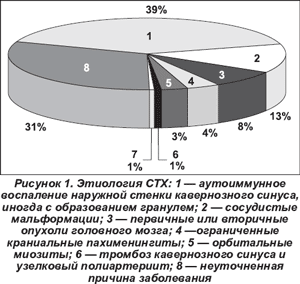

Комплексное обследование больных позволило выявить основные причины формирования СТХ (рис. 1). Наиболее частым этиологическим фактором развития заболевания было аутоиммунное воспаление наружной стенки кавернозного синуса, иногда с образованием гранулем - 52 чел. (40 %). Реже причиной СТХ были сосудистые мальформации - 17 чел. (13 %), первичные или вторичные опухоли головного мозга - 10 чел. (7,8 %), ограниченные краниальные пахименингиты - 5 чел. (4 %), орбитальные миозиты - 4 чел. (3,0 %), тромбоз кавернозного синуса и узелковый полиартериит - по 1 чел. (0,7 %). У 40 (30,8 %) больных причина заболевания осталась неуточненной, и такие случаи мы трактовали как идиопатические. Этиологический фактор развития СТХ определял некоторые эпидемиологические и клинические особенности заболевания.